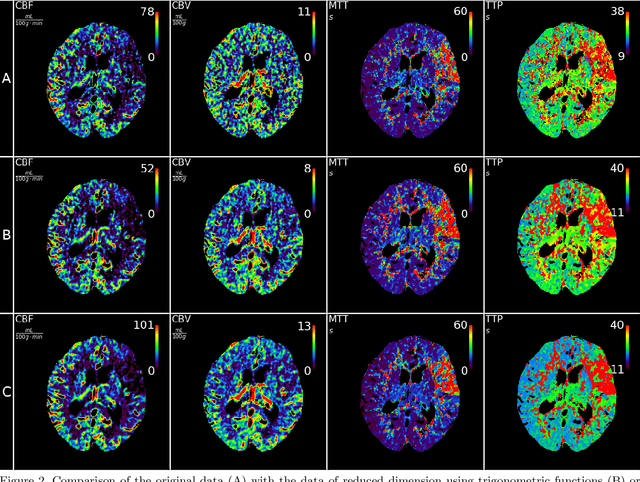

Abstract:CT perfusion imaging (CTP) plays an important role in decision making for the treatment of acute ischemic stroke with large vessel occlusion. Since the CT perfusion scan time is approximately one minute, the patient is exposed to a non-negligible dose of ionizing radiation. However, further dose reduction increases the level of noise in the data and the resulting perfusion maps. We present a method for reducing noise in perfusion data based on dimension reduction of time attenuation curves. For dimension reduction, we use either the fit of the first five terms of the trigonometric polynomial or the first five terms of the SVD decomposition of the time attenuation profiles. CTP data from four patients with large vessel occlusion and three control subjects were studied. To compare the noise level in the perfusion maps, we use the wavelet estimation of the noise standard deviation implemented in the scikit-image package. We show that both methods significantly reduce noise in the data while preserving important information about the perfusion deficits. These methods can be used to further reduce the dose in CT perfusion protocols or in perfusion studies using C-arm CT, which are burdened by high noise levels.